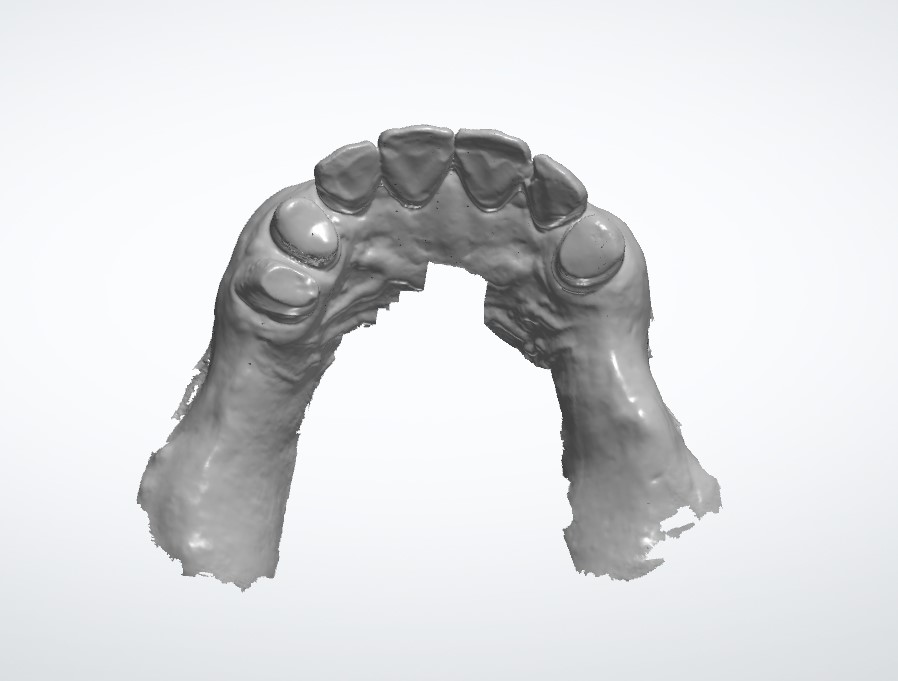

1.2. Dữ liệu bề mặt răng & nướu (File STL/PLY)

Được lấy từ máy Scan trong miệng hoặc Scan mẫu hàm.

• Yêu cầu:

• Độ chính xác cao ở các răng trụ (răng tựa cho máng).

• Lấy rõ vùng nướu và các khe răng, không bị "mù" hoặc đứt gãy dữ liệu.

• Định dạng: File .STL hoặc .PLY (có màu sắc).

rang